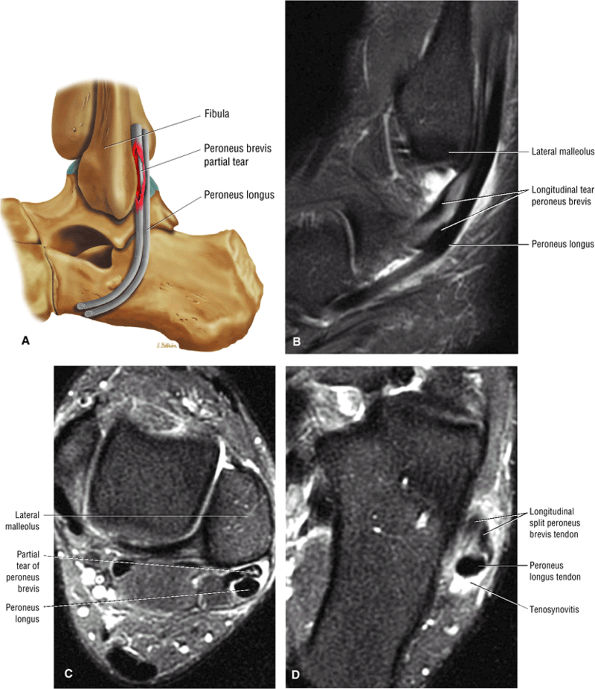

|